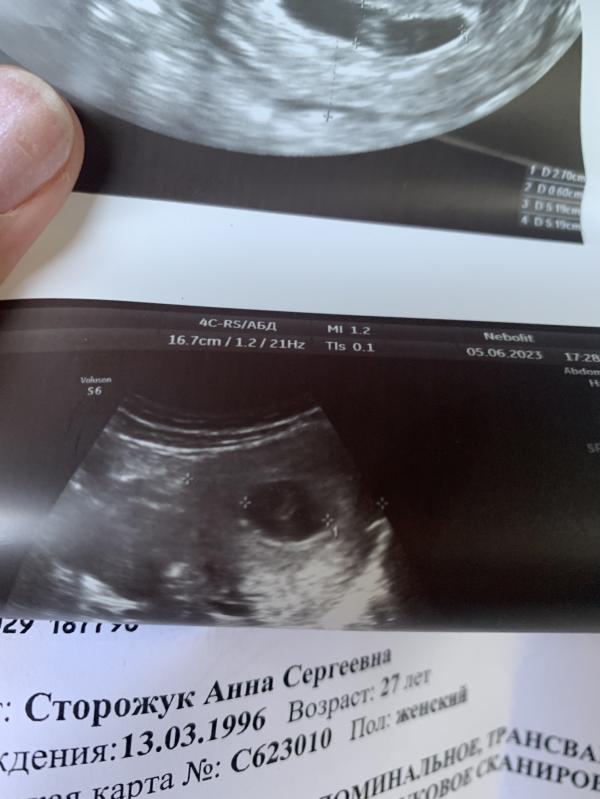

УЗИ показало только формирование эмбриона: что делать, если эмбриона не видно?

Девочки сходила на Узи сегодня,не могла терпеть долго😃

Съездила в платную,смотрел мужчина.

Эмбриона он не увидел,но увидел как идет только формирование эмбриона.Трубку увидел😌